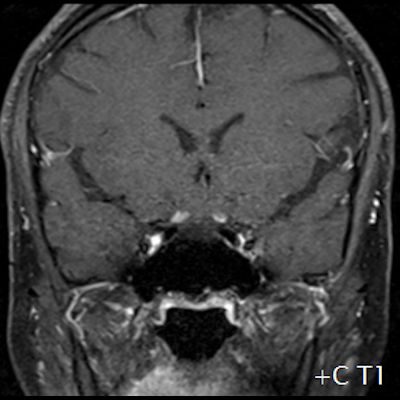

- (A) Torakal MRG’de sagital görüntülerde üst-orta torakal düzeyde T2A hiperintens (oklar), T1A izo-hipointens (ok) uzun segment ekspansil sinyal değişikliği izlenmekte olup sagital postkontrast T1A’da kontrast tutulumu mevcuttur (oklar). Bulgular longitudinal ekstensif transvers miyelit (LETM) ile uyumludur.

- (B) Orbita MRG’de aksiyel yağ baskılı T1A’da optik sinir prekiazmatik segmenti (oklar) gösterilmiş olup sırası ile aksiyel ve koronal post-kontrast yağ baskılı T1A görüntülerde bilateral optik sinir prekiazmatik segmentte kontrast tutulumu dikkati çekmektedir (oklar ve daire).

- Optik nörit varlığında özellikle optik kiazma ve posterior optik sinir tutulumu görülür ve bilateral olabilir.

- Transvers miyelit sıklıkla santral gri cevheri etkileyen ve üç veya daha fazla vertebral gövde uzunluğunu etkilemektedir (LETM).

- Kontrast madde enjeksiyonu sonrasında neredeyse tüm akut NMO lezyonları, yamalı, düzensiz veya periferik olarak kontrastlanma gösterir.